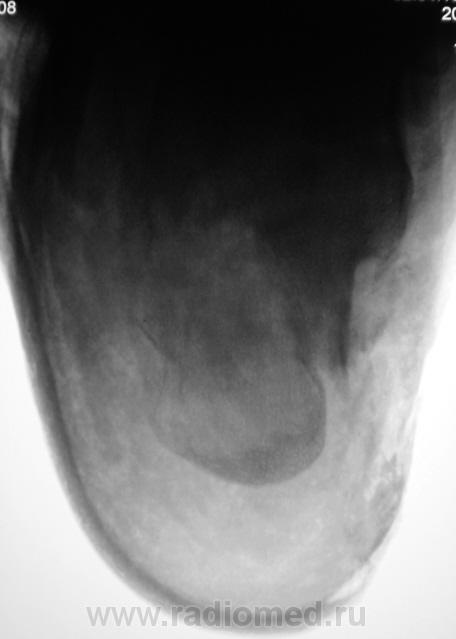

Лечение состояло из "множества рентгенов" и гипса. Срок - 5 месяцев.

Сейчас думают об остеомиелите.

Контуры пяточной кости относительно четкие, разрежение структуры пяточного бугра, в проекции перелома уплотнение структуры кости( имею в виду последние снимки).Клиника остеомиелита есть?

Во-первых, деформация пяточной кости; во-вторых, отсутствие консолидации, через некоторое время и ложный сустав сформируется. Неоднородное уплотнение костной структуры в теле кости может быть обусловдено как остеомиелитом, так и перераспределением нагрузки.

Признаков остеомиелита не вижу, только консолидир перелом с неуд стоянием отломков.